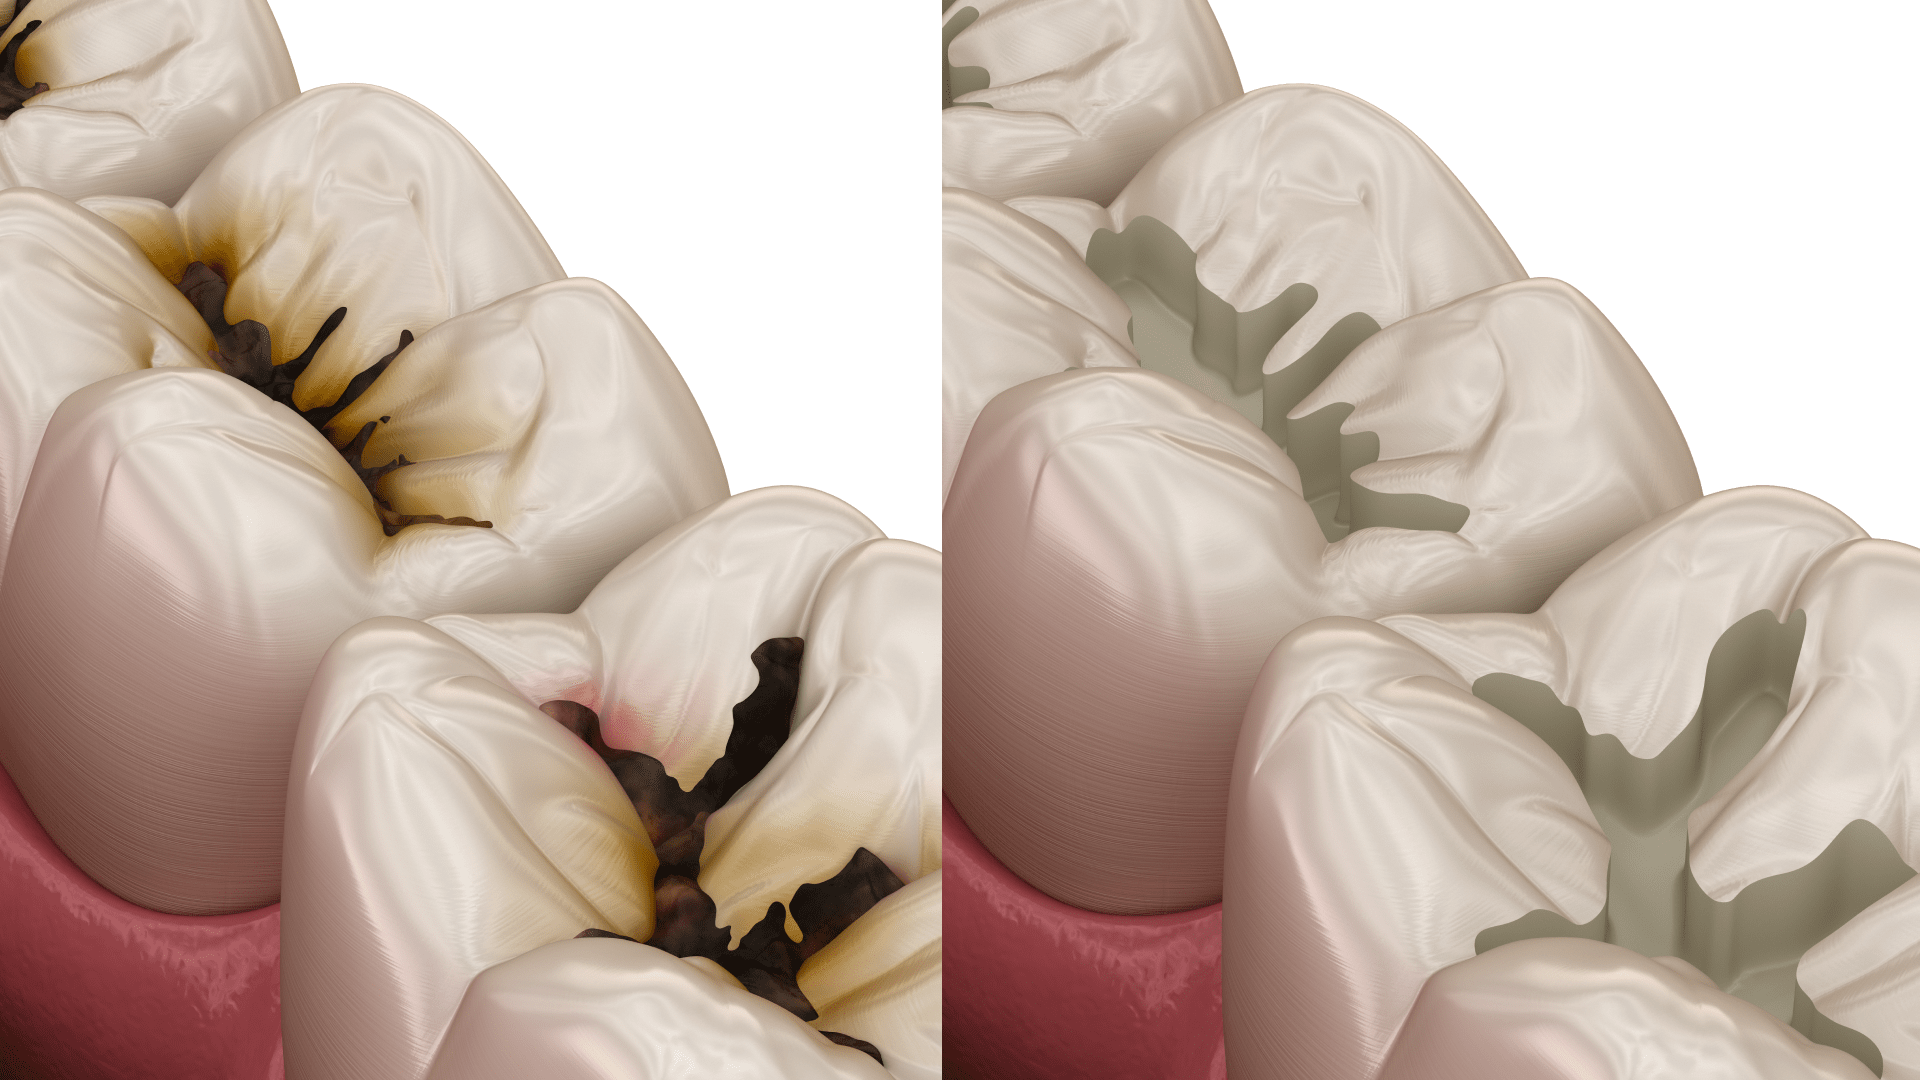

Як виглядає карієс на зубах? На початкових стадіях він проявляється як невелика біла або матова пляма на поверхні емалі. У міру розвитку захворювання вона темніє, з’являються коричневі або чорні ділянки. Поступово в зубі формується каріозна порожнина, яка може збільшуватися в розмірах.

Середній карієс

На цій стадії розвитку карієсу захворювання поширюється глибше та уражає дентин — тканину, що розташована під емаллю. У зубі формується каріозна порожнина, яка поступово збільшується. У пацієнта може з’являтися дискомфорт під час жування, підвищена чутливість або періодичний біль.

Глибокий карієс

Це найнебезпечніша стадія карієсу. Каріозна порожнина збільшується, а інфекція уражає значну частину дентину та наближається до пульпи (нервово-судинного пучка зуба). На цьому етапі біль стає більш вираженим і може виникати навіть без зовнішніх подразників. Без лікування глибокий карієс часто призводить до серйозних ускладнень.

- Видалення уражених тканин. Лікар очищує зуб від каріозної тканини. Для цього використовується бормашина або сучасні щадні методики обробки зуба. Основне завдання — повністю усунути інфіковані ділянки та зупинити подальший розвиток захворювання.

- Підготовка каріозної порожнини. Після видалення уражених тканин лікар обробляє порожнину антисептичними засобами та готує зуб до подальшого відновлення.

- Пломбування зуба. Очищену порожнину заповнюють спеціальним пломбувальним матеріалом. Для цього використовуються композити, які добре відновлюють форму зуба та мають естетичний вигляд.